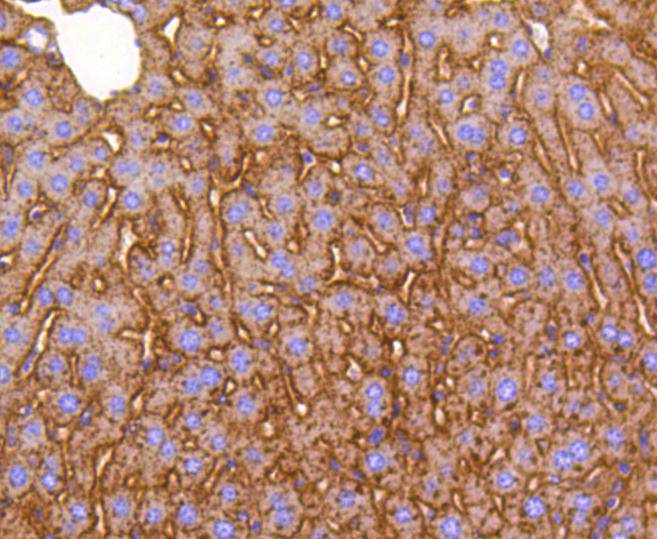

![DIABLO Rabbit mAb[48991]](https://img1.dxycdn.com/p/s14/2025/0923/295/8824809712616140791.jpg)

,